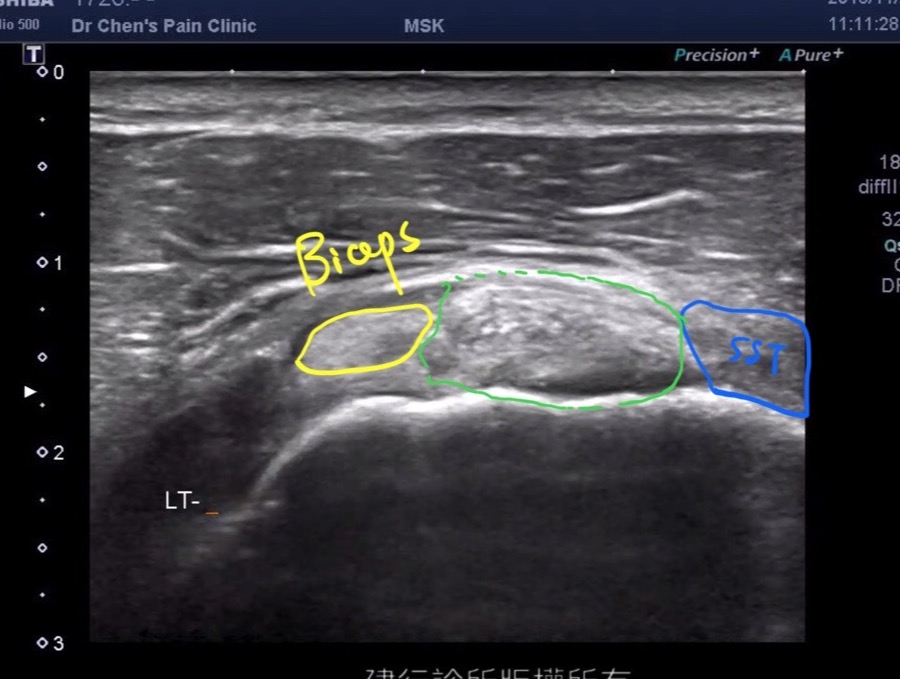

Biceps anchor tendinosis

可以見到二頭肌因為脊上肌肌腱斷裂造成二頭肌往內移動,以及二頭肌肌腱明顯腫大發炎的現象